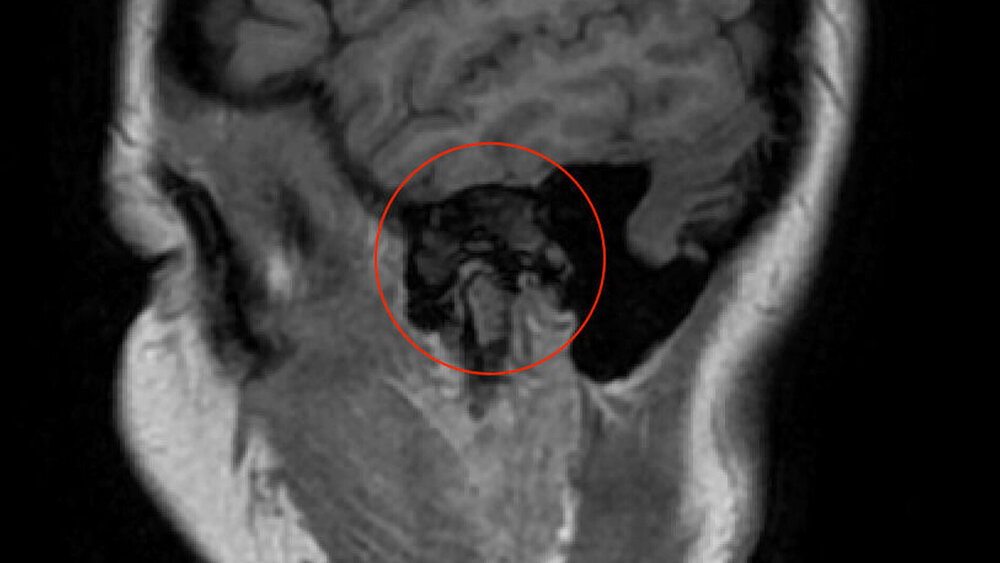

Zufallsbefund eines Riesenzelltumors bei langjähriger Bruxismus-Patientin